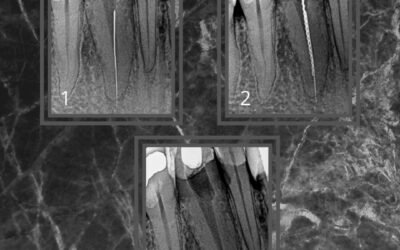

Lima Fraturada que ultrapassou o forame Apical

Neste caso, enviado por um colega, havia uma lima fraturada que ultrapassava o forame apical. Devido à grande dificuldade de remoção, por ela estar travada no forame, foi necessário usar uma lima Hedstroem com cola. E assim foi possível executar a...

Remoção de Lima Fraturada

Existem várias técnicas para remoção de instrumentos fraturados no canal e é bom que o Endodontista conheça todas elas, pois a cada caso uma determinada técnica pode funcionar em detrimento das outras. Para a remoção de lima fraturada ou qualquer...